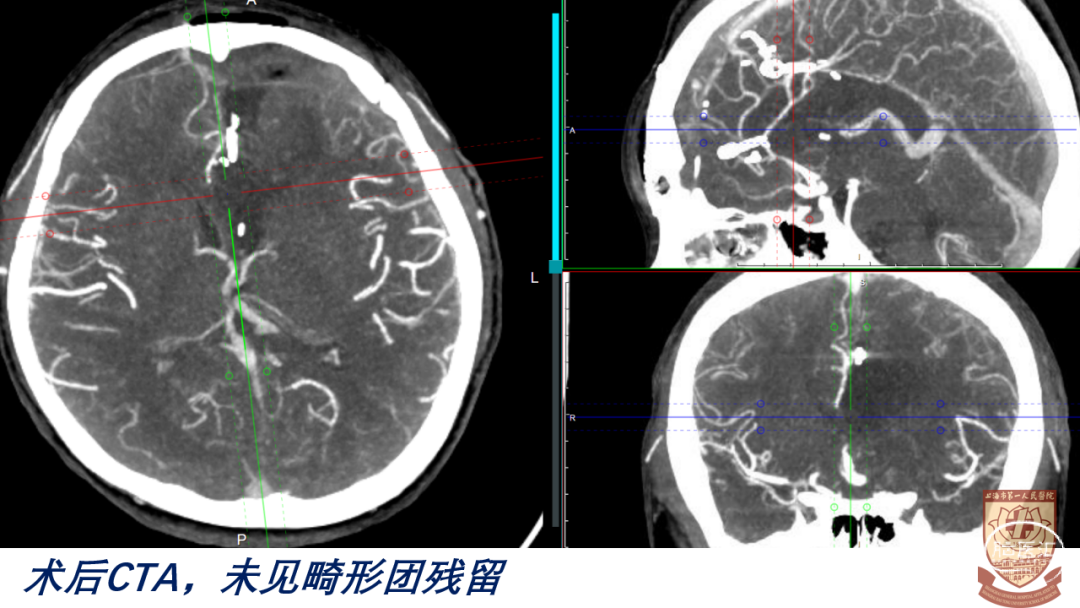

04

结果

术后GCS15分,言语正常,肢体感觉、肌力正常

脑室引流管顺利夹管、拔除

正常出院,无明显神经功能障碍